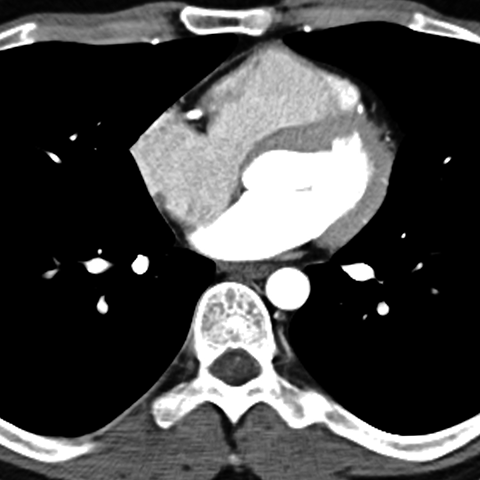

Normal Heart (CT) [6 of 6]